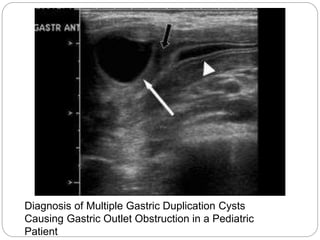

Diagnosis of Multiple Gastric Duplication Cysts

Causing Gastric Outlet Obstruction in a Pediatric

Patient

Contrast-enhanced computed tomography image of the abdomen

showing a well-circumscribed, low-attenuation fluid collection seen in

relation to the greater curvature of the stomach with rim enhancement,

suggestive of an intestinal duplication